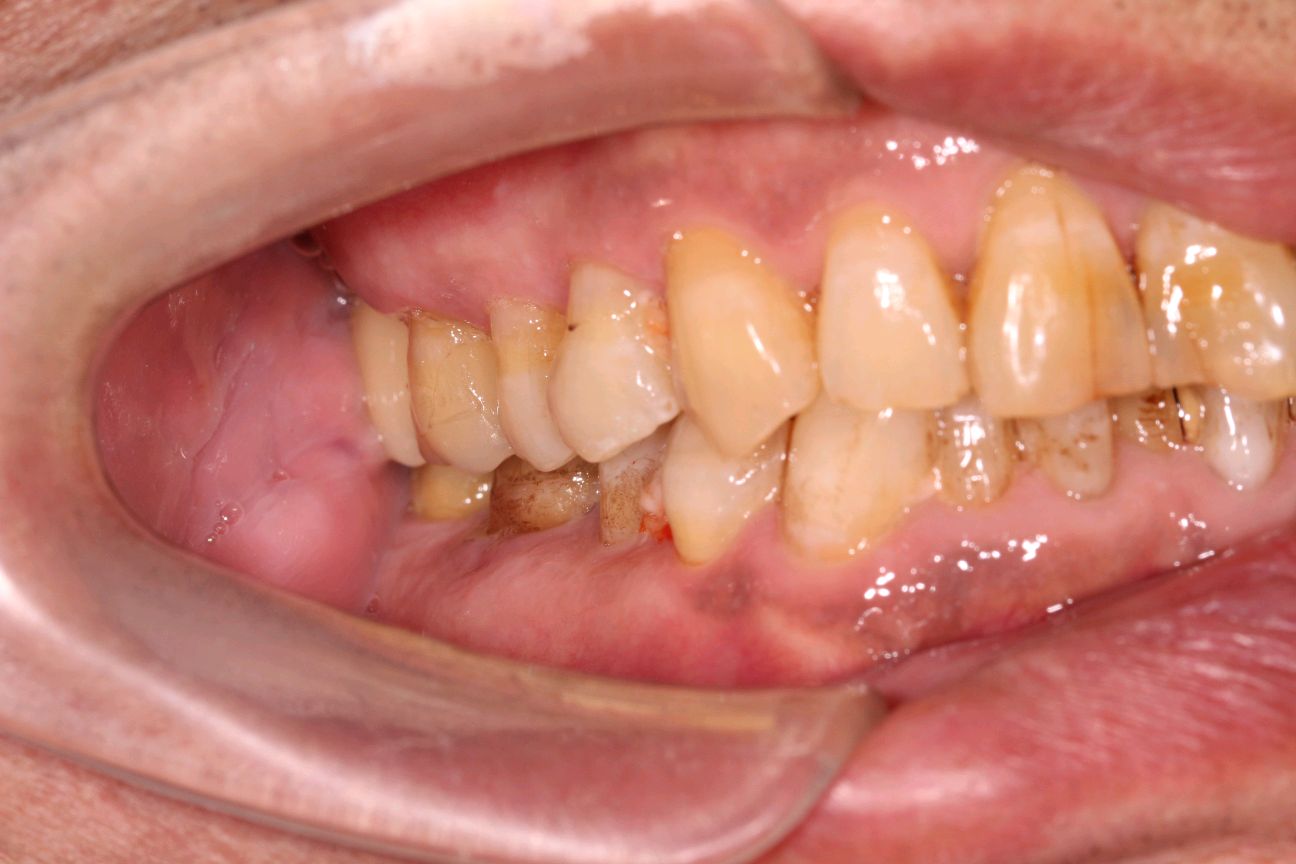

患者是成功人士,平时非常忙碌,忽略了口腔健康,直到有一天无法咀嚼食物后才想到要治疗牙齿,我们为他摄了CBCT,发现有重度牙周病,上合双侧7自然脱落,左上8,III度松动,并近中倾斜移位,对合牙严重伸长,还有其他牙齿疾患,需要综合治疗;经过牙周病治疗、上合窦骨增量、上合种植修复、拔牙、截冠、根管治疗、桩冠、高嵌体修复等!时间长达一年,终于恢复了正常牙列!可以享受食物的美好!